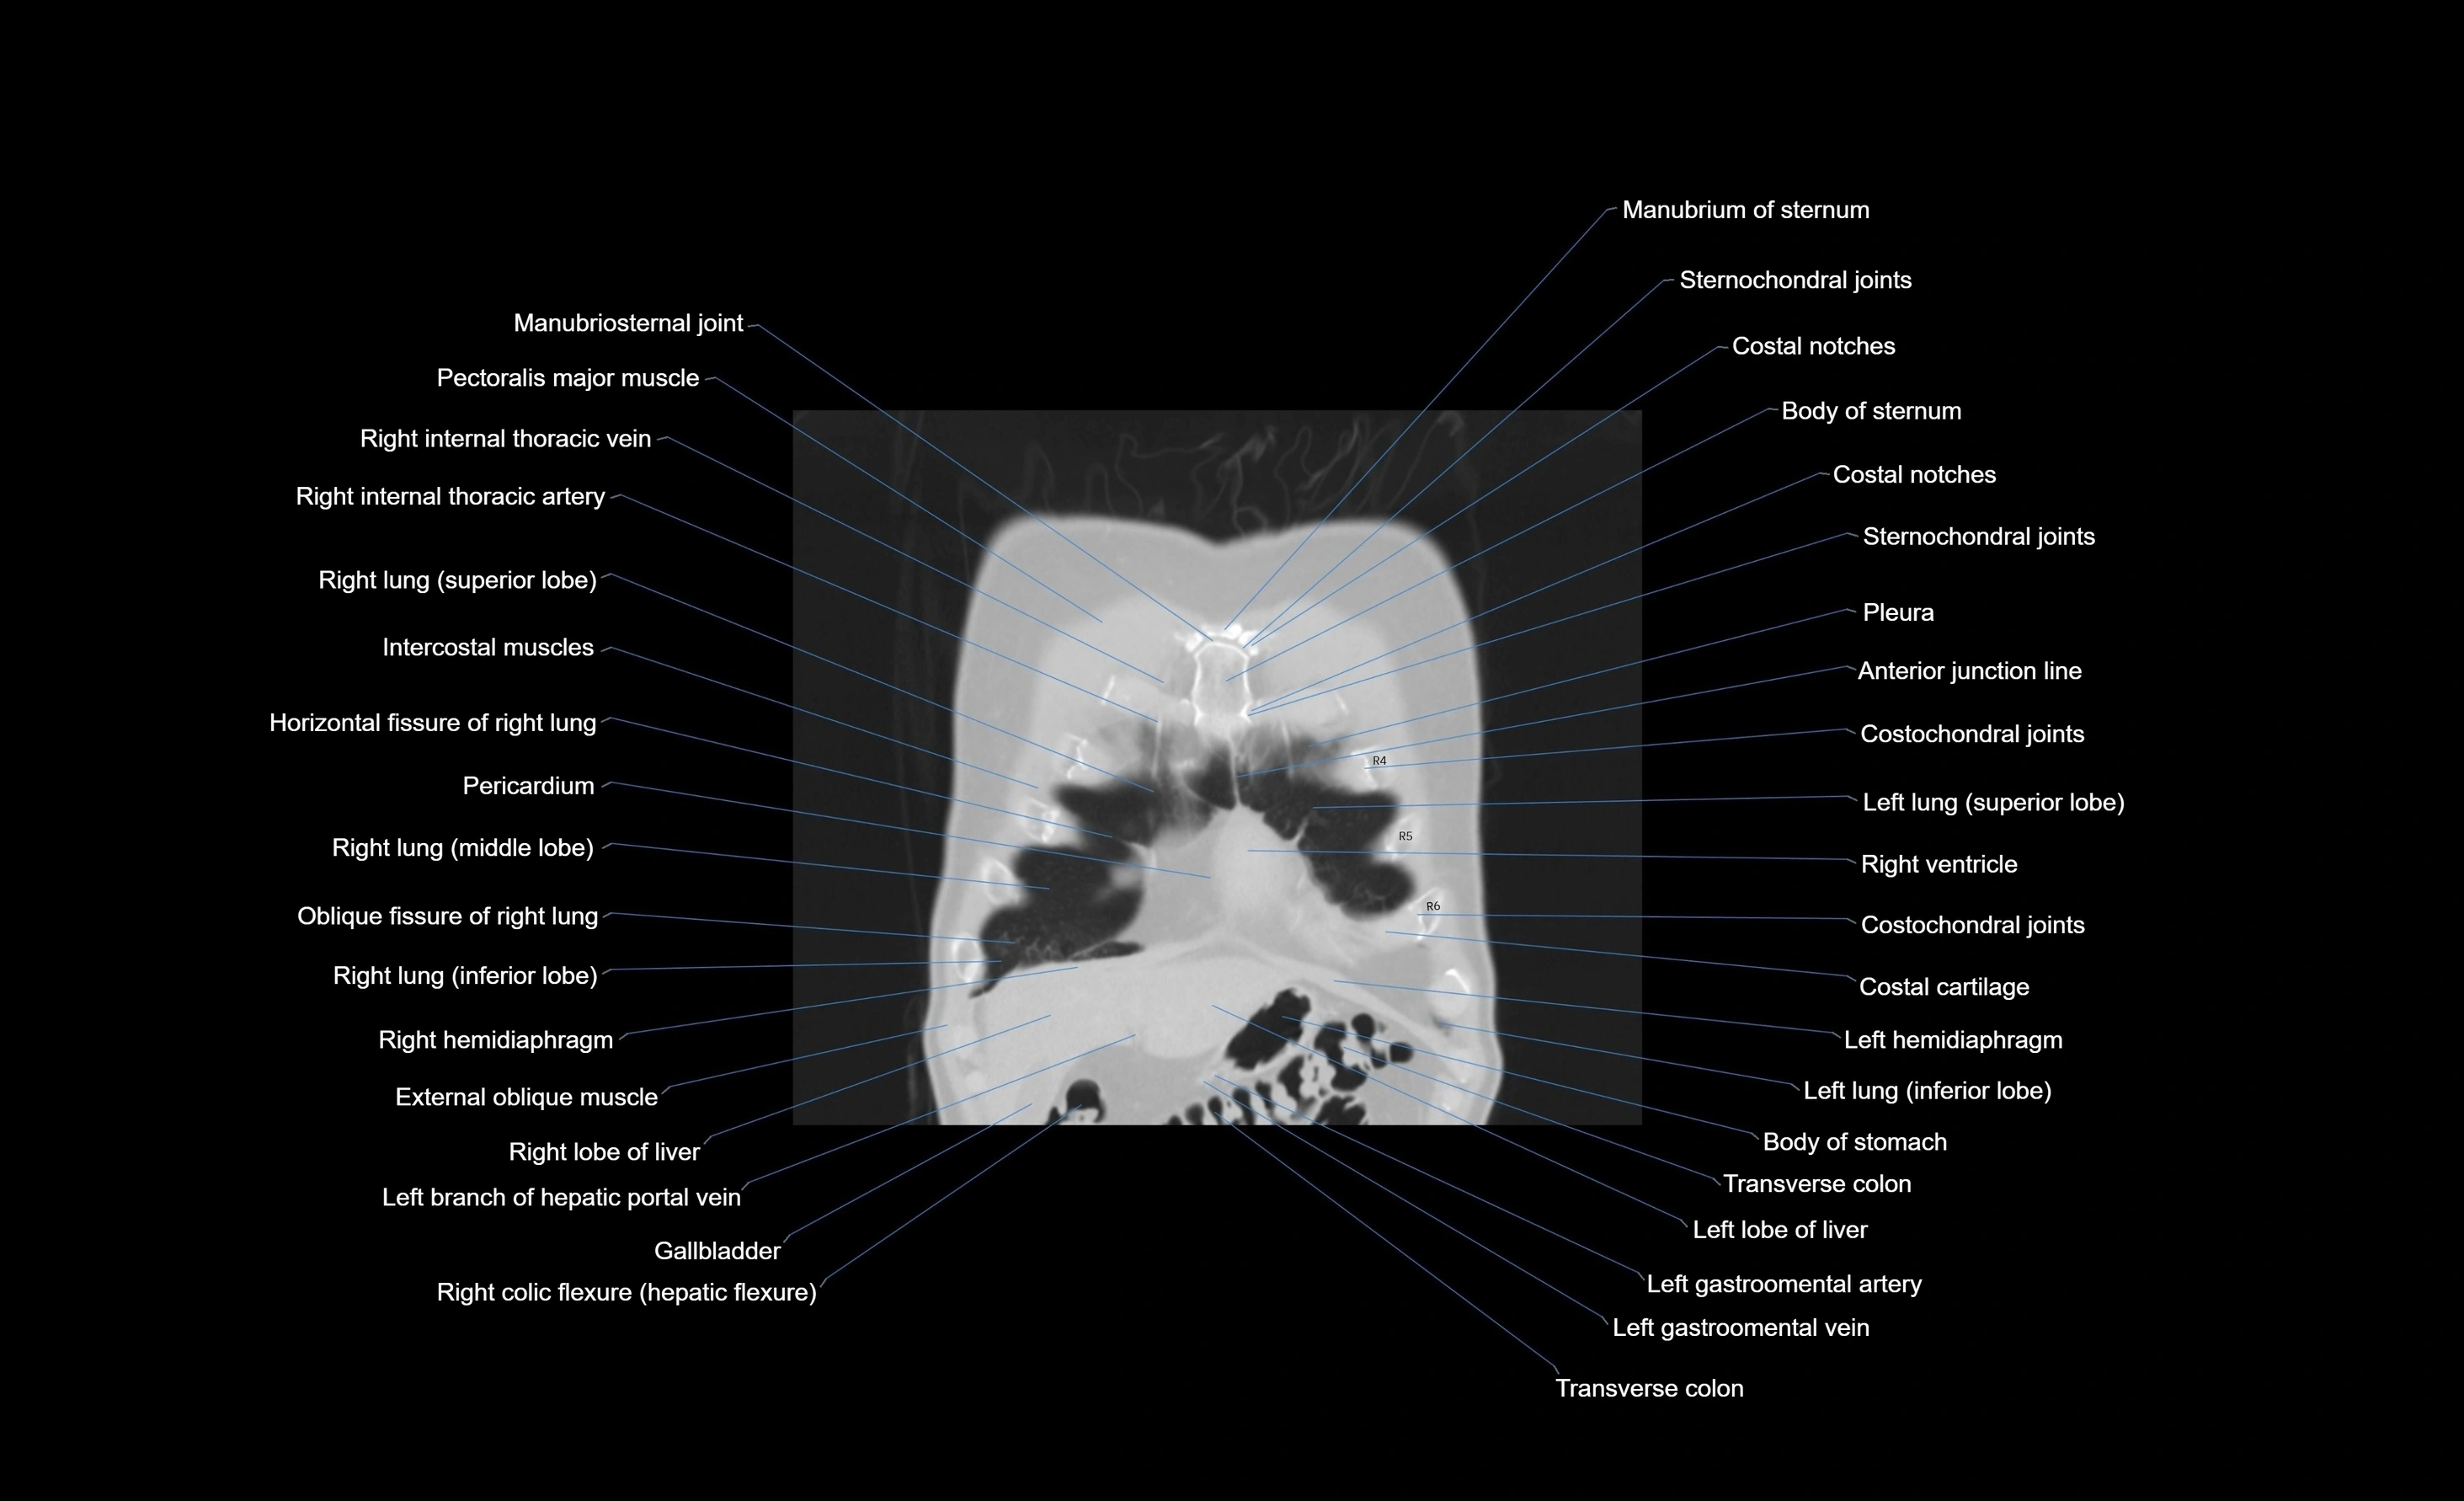

CT images